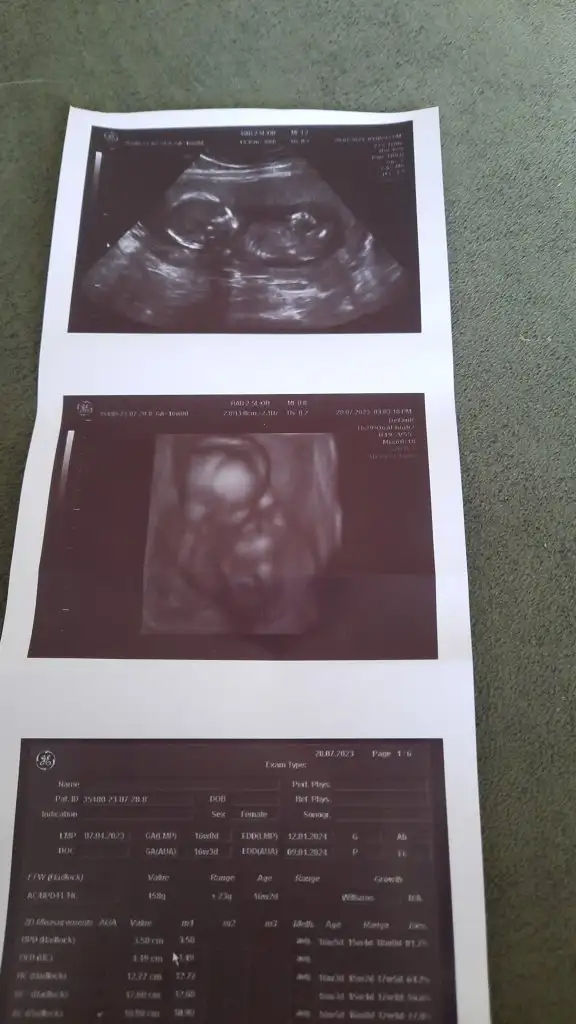

Maşallah canım aynı hisler her defasında bende de oluyorKızlar kontrolüm vardı bugün çok şükür iyii her gittiğimde o masaya yatarken kalbim cikacakmis gibi oluyor 14 cm 160 grm olmusuzEki Görüntüle 3278619

Bugün benimde kontrolüm vardı. Benim bebişim de 160 grKızlar kontrolüm vardı bugün çok şükür iyii her gittiğimde o masaya yatarken kalbim cikacakmis gibi oluyor 14 cm 160 grm olmusuzEki Görüntüle 3278619